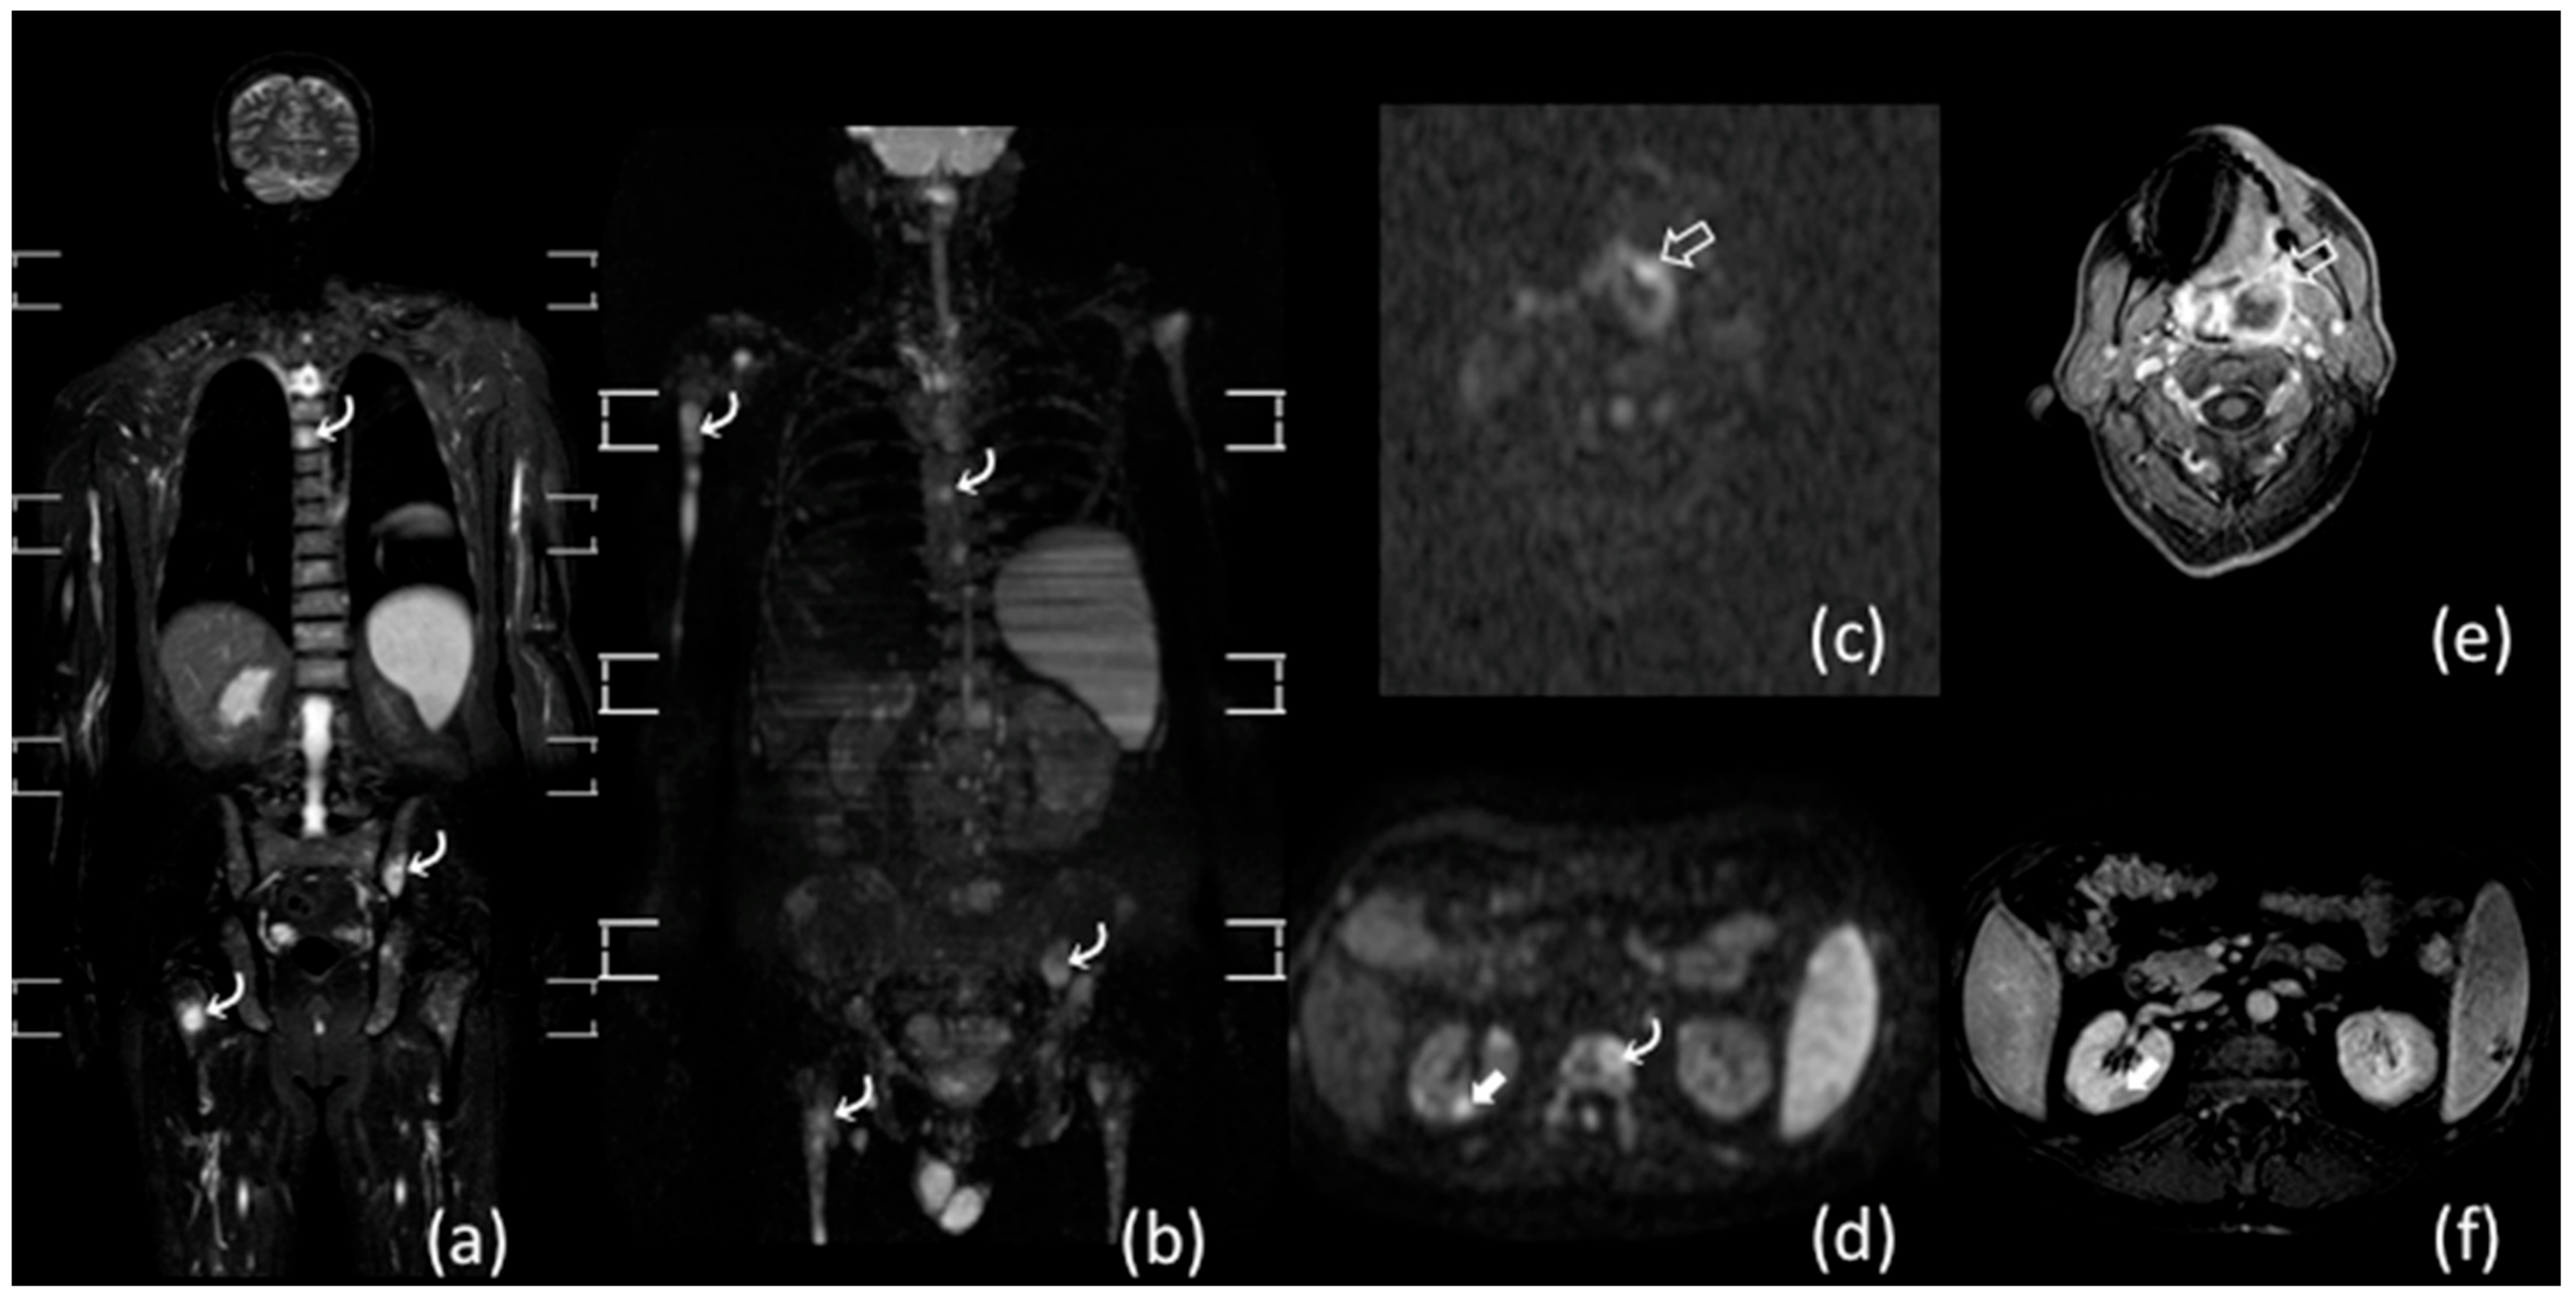

- Albano, D.; Patti, C.; La Grutta, L.; Agnello, F.; Grassedonio, E.; Mulè, A.; Cannizzaro, G.; Ficola, U.; Lagalla, R.; Midiri, M.; et al. Comparison between whole-body MRI with diffusion-weighted imaging and PET/CT in staging newly diagnosed FDG-avid lymphomas. Eur. J. Radiol. 2016, 85, 313–318. [Google Scholar] [CrossRef] [PubMed]

- Lin, C.; Luciani, A.; Itti, E.; El-Gnaoui, T.; Vignaud, A.; Beaussart, P.; Lin, S.-J.; Belhadj, K.; Brugières, P.; Evangelista, E.; et al. Whole-body diffusion-weighted magnetic resonance imaging with apparent diffusion coefficient mapping for staging patients with diffuse large B-cell lymphoma. Eur. Radiol. 2010, 20, 2027–2038. [Google Scholar] [CrossRef]

- Kwee, T.C.; Vermoolen, M.A.; Akkerman, E.A.; Kersten, M.J.; Fijnheer, R.; Ludwig, I.; Beek, F.J.; van Leeuwen, M.S.; Bierings, M.B.; Bruin, M.C.; et al. Whole-body MRI, including diffusion-weighted imaging, for staging lymphoma: Comparison with CT in a prospective multicenter study. J. Magn. Reson. Imaging 2014, 40, 26–36. [Google Scholar] [CrossRef]